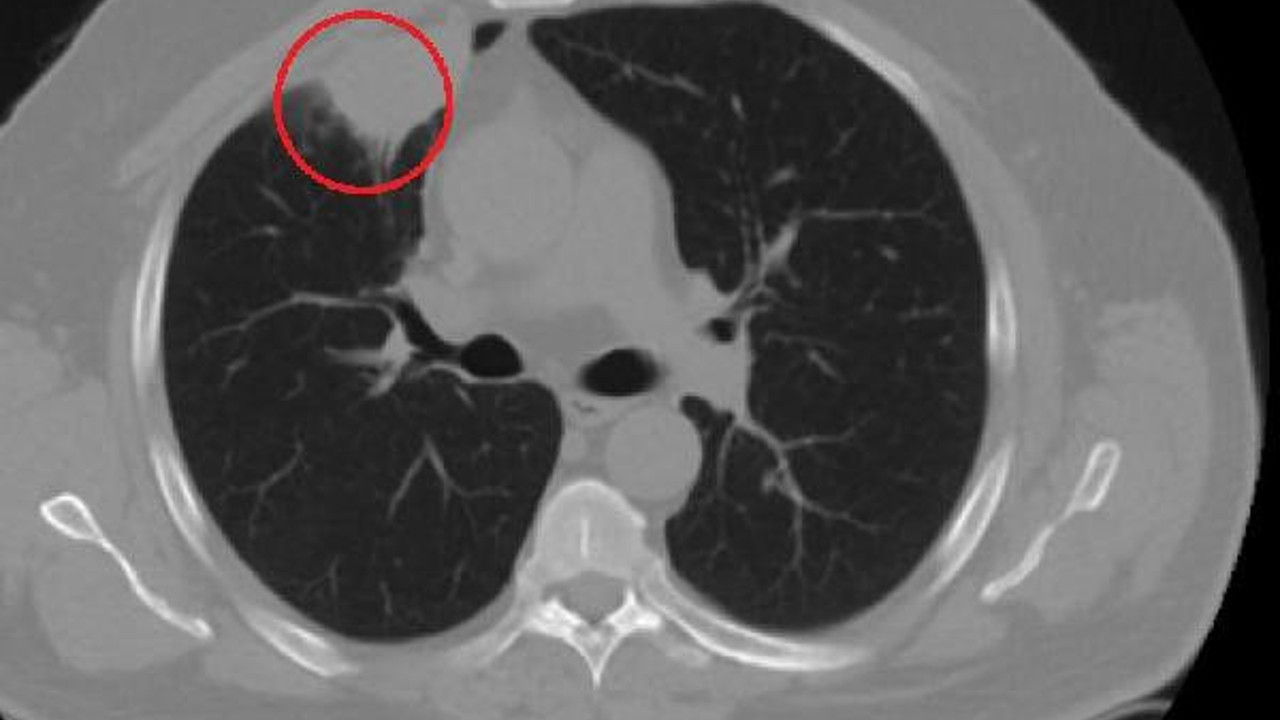

Kent dışında çalışan N.T.''nin, göğüs ağrısı şikayetiyle gittiği hastanede çekilen tomografisinde sağ akciğerinde 4 santimetre çapında tümör tespit edildi. Kanser olabileceği şüphesiyle yapılan ileri tetkikler sonrası N. T.''ye akciğer kanseri teşhisi kondu ve acil ameliyat kararı verildi. Bunun üzerine N.T., ameliyat için memleketi Kahramanmaraş''a geldi. Sütçü İmam Üniversitesi Sağlık Uygulama ve Araştırma Hastanesi Göğüs Cerrahi Anabilim Dalı Öğretim Üyesi Dr. Fatoş Kozanlı da tomografi ve test sonuçlarına göre N. T.''ye akciğer kanseri teşhisi koydu ve ameliyat yapılması gerektiğini söyledi.

"Hastamız, çalıştığı başka bir kentte göğsünden darbe alıyor ve ağrıları geçmeyince bir üniversite hastanesine başvuruyor. Burada hastaya bir akciğer grafisi çekiliyor. Sağ akciğerinde bir kitleye rastlanıyor. Daha sonra hastaya, bir akciğer tomografisi çekiliyor ve göğüs cerrahisi için önemli büyüklükte olan 4 santimetre çapında, akciğer kanserine benzer özellikte radyolojik bulgular olan bir kitle tespit ediliyor. Daha sonra hastaya yapılan ileri tetkiklerde akciğer kanseri teşhisi konuluyor. Hastaya bir cerrahi planlanıyor. Hasta Kahramanmaraşlı olduğu için kendi memleketine gelmeyi tercih ediyor. Bize başvurdu ve göğüs ağrısı şikayeti vardı. Öksürük, nefes darlığı, balgam çıkarma, ateş gibi şikayetleri yoktu. Hastayı biz de değerlendirdik ve ameliyat olmasına karar verdik. Çünkü akciğer kanserine çok benzer radyolojik bulguları vardı. Sağlık Bakanlığımızın kuralları gereği her hastayı ameliyat öncesi PCR testi yapılır. Biz de ameliyat gecesi hastadan PCR testi aldık ve testi pozitif geldi. Ameliyatımızı 14 gün erteledik ve hastamıza koronavirüs tedavisi uygulandı. Hasta 14''üncü gün tekrar bize başvurdu ve yapılan PCR testi negatif çıktı. Yeni bir tomografi çektik ve tümörün tamamen ortadan kalktığını gördük. Şimdi sonuç bilgilerinden başlangıca gittiğimizde, bu bir akciğer kanseri olsaydı, ortadan kalkması mümkün değildi. Başka bir patolojiye bağlı durum olsaydı, yine verdiğimiz tedaviyle ortadan kalkmasını çok beklemeyiz. Antiviral tedavisi verdik ve hastanın radyolojik bulguları neredeyse tamamen normale döndü. Hastaya bunu izah ettik, ''Dünya literatüründe hiç görülmeyen bir radyolojik bulgu'' diyerek. Bu gördüğümüz manzara artık hastanın akciğer grafisinde yok, akciğer kanseri değil. "